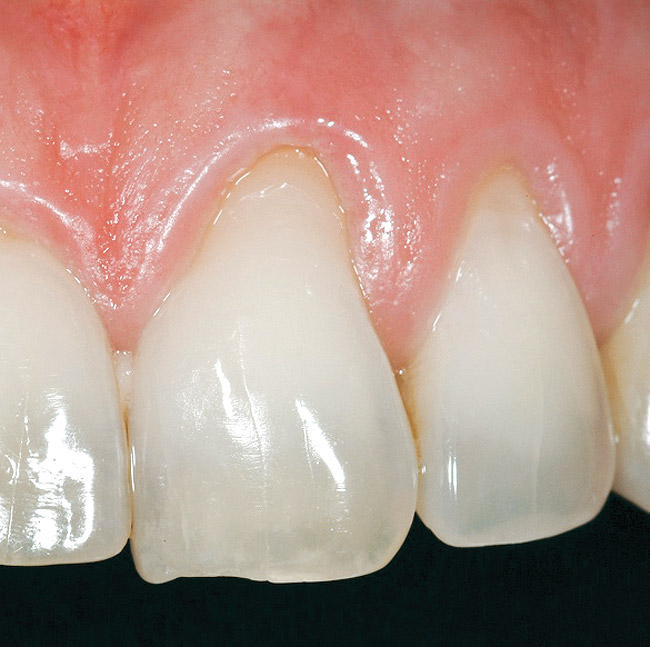

The outline of the pre-existing facial margin can be seen in Figure 18, approximately 0.75 mm from the facial aspect of the temporary restoration. Also note the symmetry between the facial aspect of the clinical crown on tooth No. 8, and provisional restoration of tooth No. 9. Preceding fixation of the dermis, PRP was applied. The PRP-enhanced dermis was then placed over the root surface (Figure 19) and secured with 4.0 vicryl sutures in a sling fashion around tooth No. 9. Additional application of PRP preceded a tension-free flap closure, totally covering the dermis with the pre-existing facial gingival tissues. Closure was accomplished with 4.0 vicryl sutures using a horizontal mattress and continuous sling suturing method. Additional application of PRP over the surgical site served as a bioactive wound dressing.37-39

Figure 19  Case Two Dermal matrix graft secured.

Figure 19